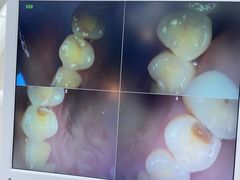

• 牙博士口腔品牌连锁(杨浦店)

• -牙博士口腔品牌连锁(杨浦店)

匿名用户 | 22-02-19

木南可可1112 | 22-02-19